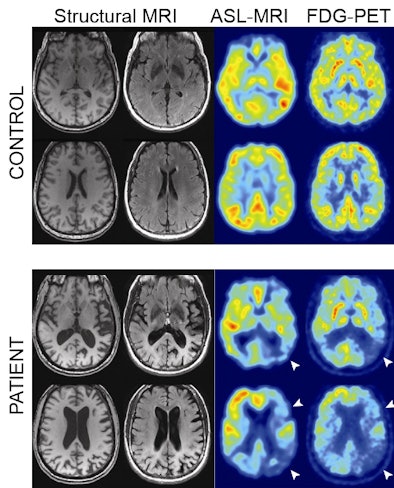

| Structural MRI, ASL-MRI, and FDG-PET images from control subjects (top row) and Alzheimer's patients (bottom row). All four patients were diagnosed correctly by both readers using both modalities. White arrows highlight areas of concordant hypometabolism on FDG-PET and hypoperfusion on ASL-MRI. Image courtesy of the Perelman School of Medicine. |

In the first study, published in Alzheimer's and Dementia, researchers obtained FDG-PET and ASL-MR images concurrently in 17 Alzheimer's patients and 19 age-matched control subjects. They paired the results with FDG-PET and ASL-MR images from 19 control subjects and 15 Alzheimer's patients to perform a qualitative analysis.

Both modalities revealed similar regional abnormalities in Alzheimer's disease, as well as comparable sensitivity and specificity for detecting the disease after visual review by two readers.